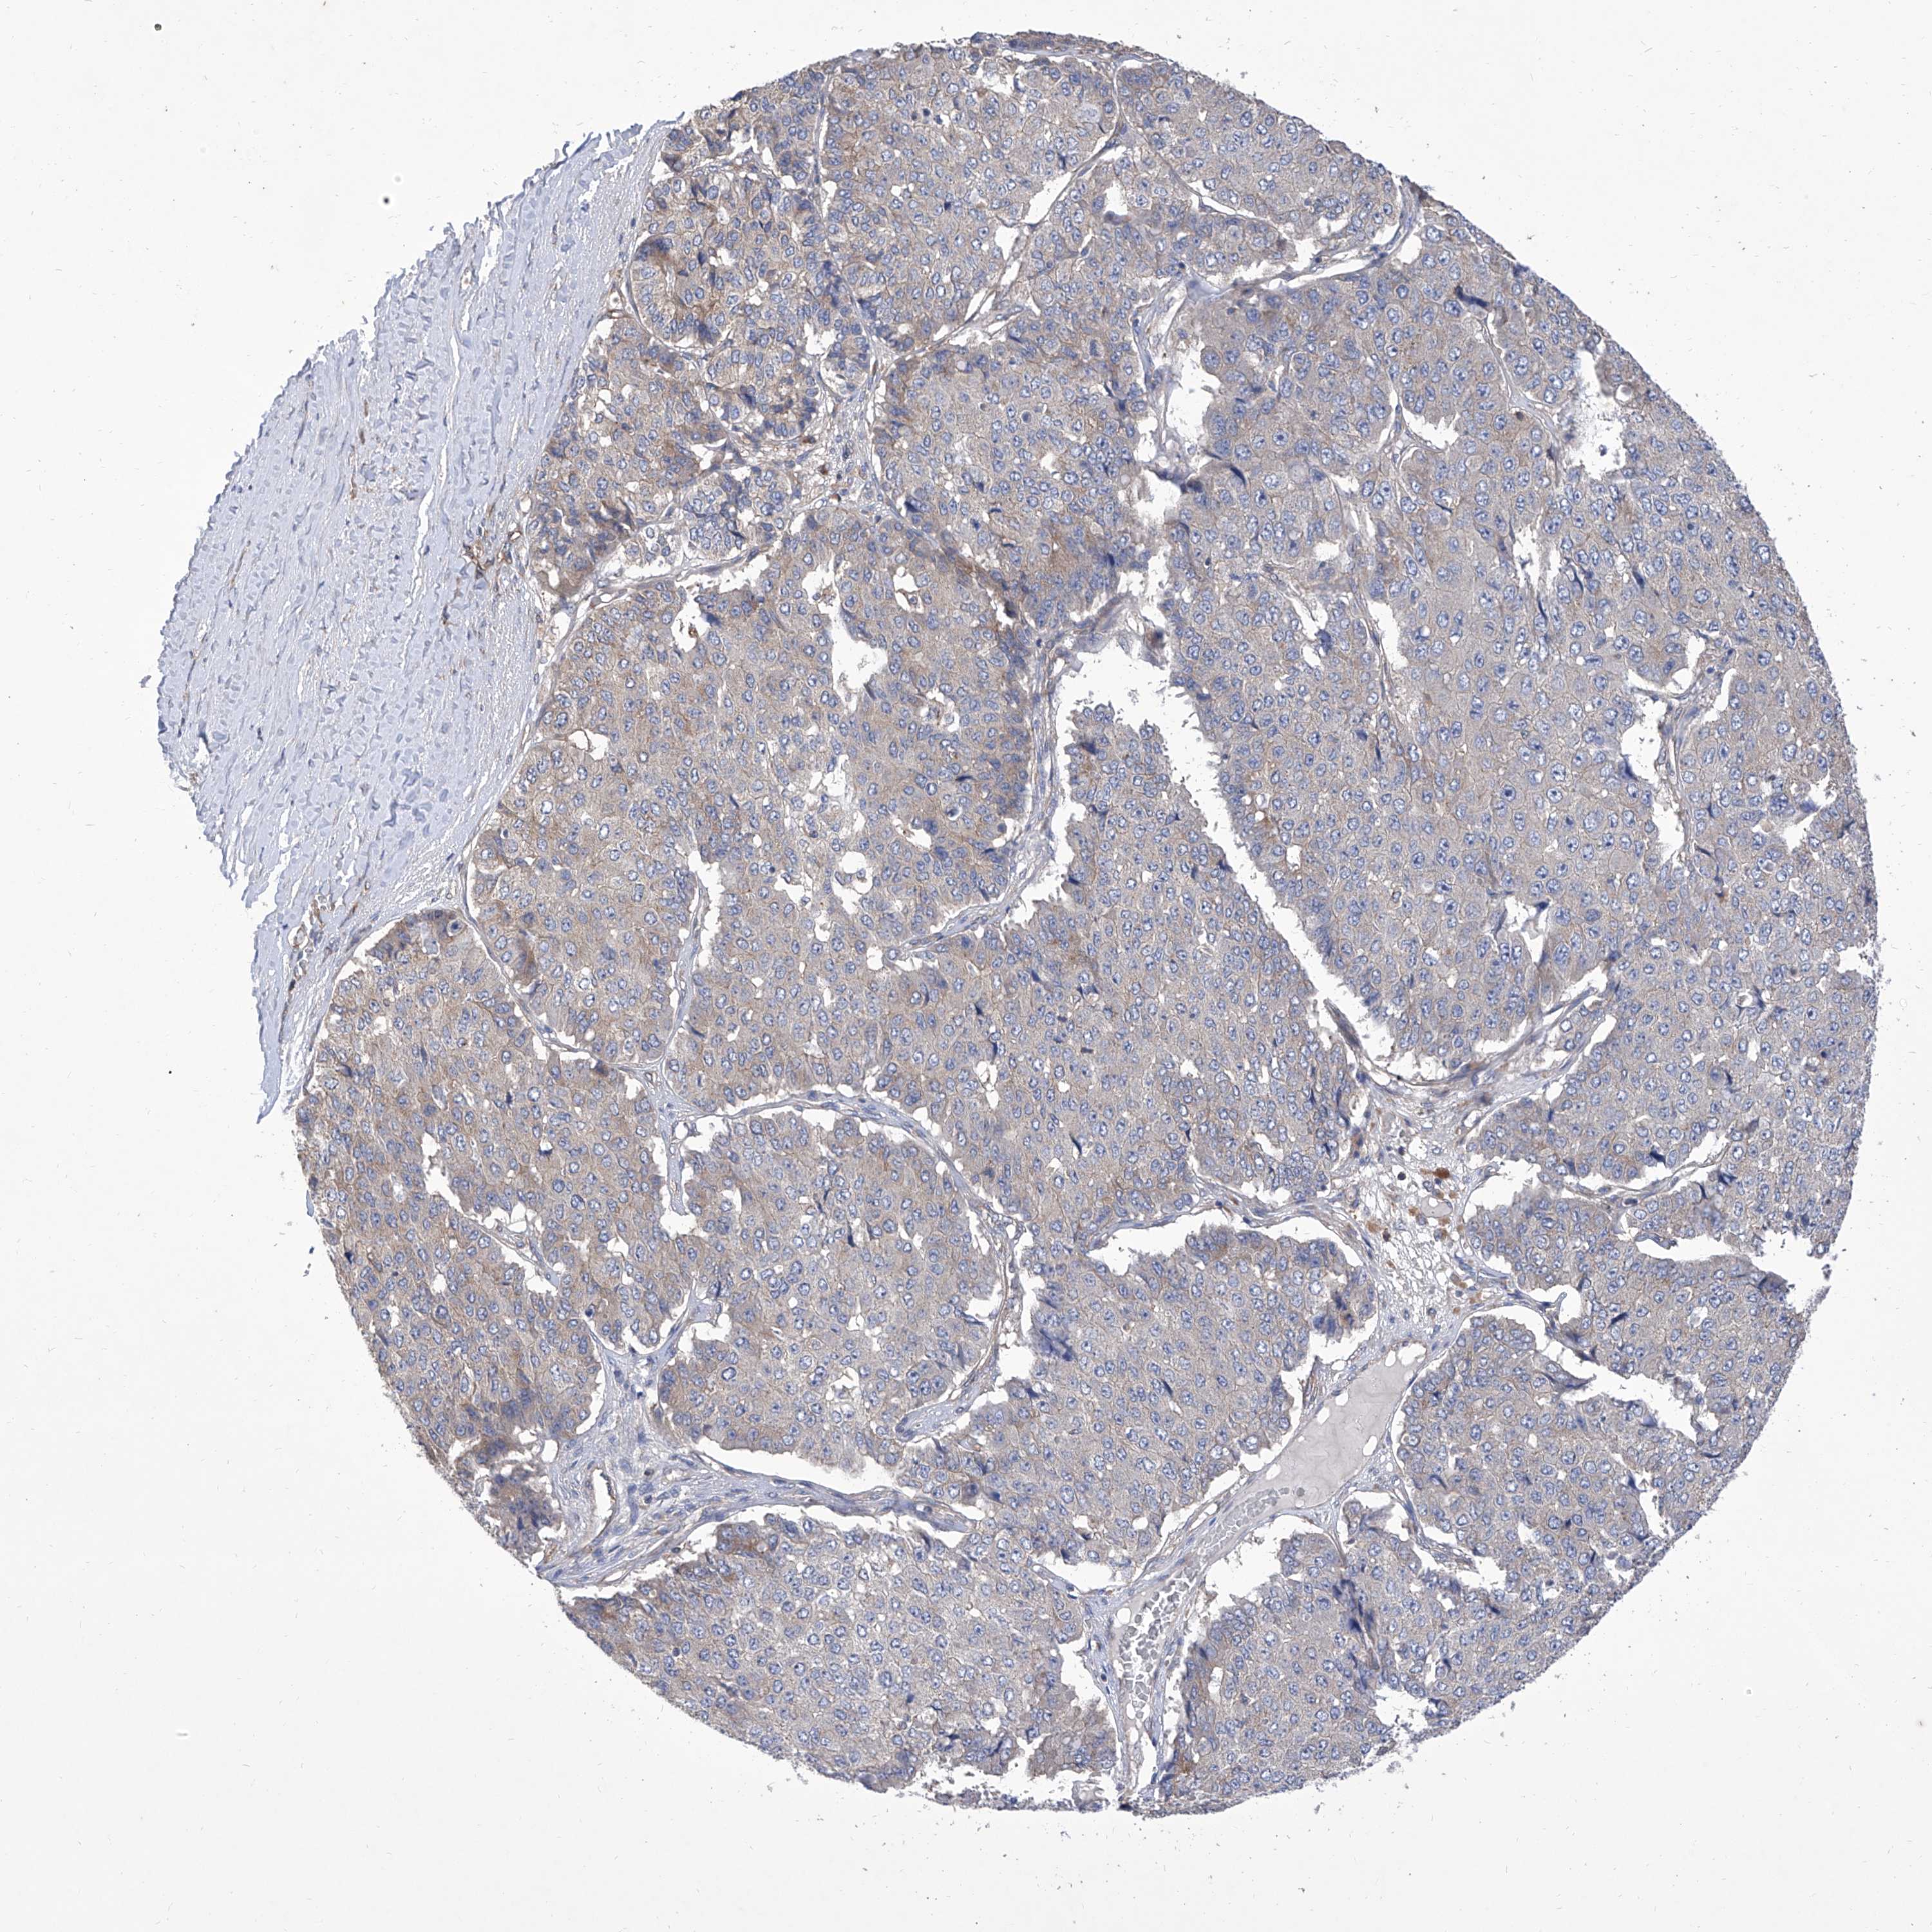

PANCREATIC CANCER - Protein expressioni

A mouse-over function shows sample information and annotation data. Click on an image to view it in a full screen mode. Samples can be filtered based on level of antibody staining by selecting one or several of the following categories: high, medium, low and not detected. The assay and annotation is described here.

Note that samples used for immunohistochemistry by the Human Protein Atlas do not correspond to samples in the TCGA dataset.

Antibody stainingi

Antibody staining in the annotated cell types in the current human tissue is reported as not detected, low, medium, or high, based on conventional immunohistochemistry profiling in selected tissues. This score is based on the combination of the staining intensity and fraction of stained cells.

Each image is clickable and will lead to virtual microscopy that enables deeper exploration of all samples and also displays staining intensity scores, fraction scores and subcellular localization as well as patient and tissue information for each sample.

Antibody HPA030164

Antibody HPA030165

Antibody HPA030166

Adenocarcinoma, NOS